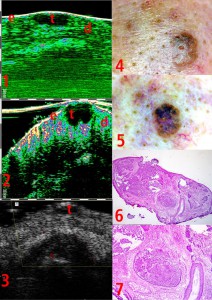

-Υπέρηχος Υψηλής Συχνότητας (HFUS) και Ιστολογία

-Μελάνωμα

-Μέτρηση επιπέδων Breslow και Klark σε έμβιο οργανισμό (IN VIVO)

-Διαφοροποίηση τύπων βασικοκυτταρικού καρκινώματος